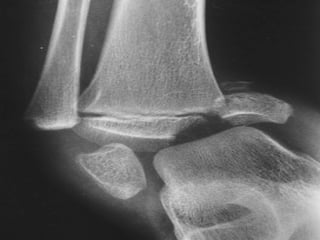

CLASIFICACIÓN PARA LAS  EPIFISIOLISTESIS SALTER HARRIS